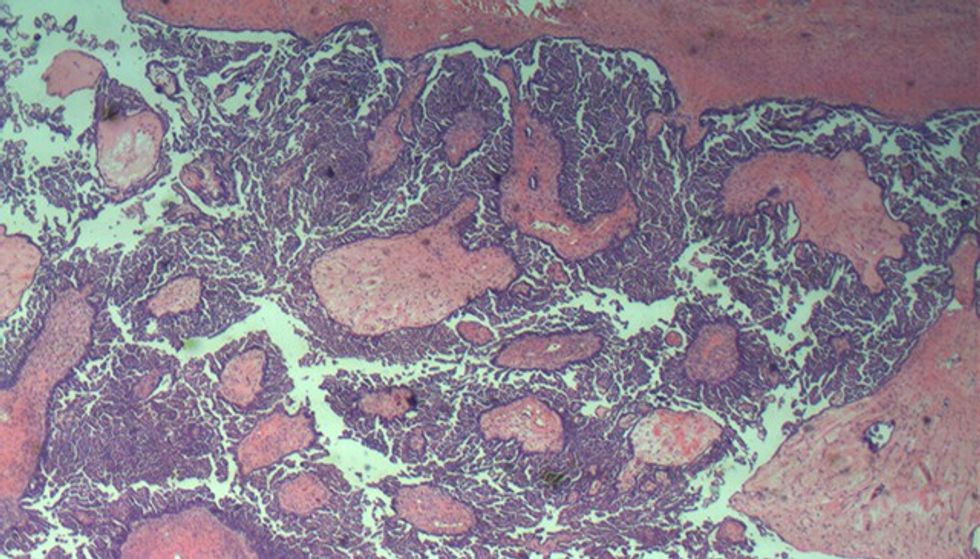

Diagnoza definitive (a bëhet fjalë për tumor beninj cystadenome, për tumor malinj-karcinomë ose tumor kufitar- borderline), bëhet gjatë ekzaminimit histopatologjik të tumorit.

Parakusht për terapi adekuate te tumori borderline i vezores, është diagnostikimi me kohë (patologu me përvojë dhe përpunimi i shumë blloqeve të parafinës me tumor - çdo 1 cm e tumorit do të duhej të ekzaminohet nën mikroskop).

Rezultati histopatologjik tregon se kemi të bëjmë me tumor borderline të vezores së majtë.